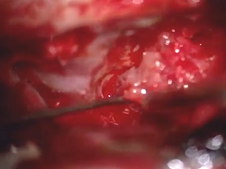

Microdirect Laryngoscopy with CO2 Laser Wedge Excisions for Subglottic Stenosis

- Date : 01/01/2020